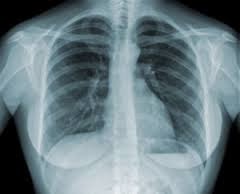

El mesotelioma pleural : Un tipo de cáncer de pulmón que asalta la pleura que abarca los pulmones , éste es el tipo más común de mesotelioma , que afecta a aproximadamente dos tercios de todos los pacientes con mesotelioma . Los síntomas incluyen horseness , fiebre, sangre en el esputo , con los brazos hinchados y confrontar , tos , pérdida de exceso de peso , dificultad para respirar , dolor de pecho , músculos débiles , y bajaron la sensibilidad táctil .